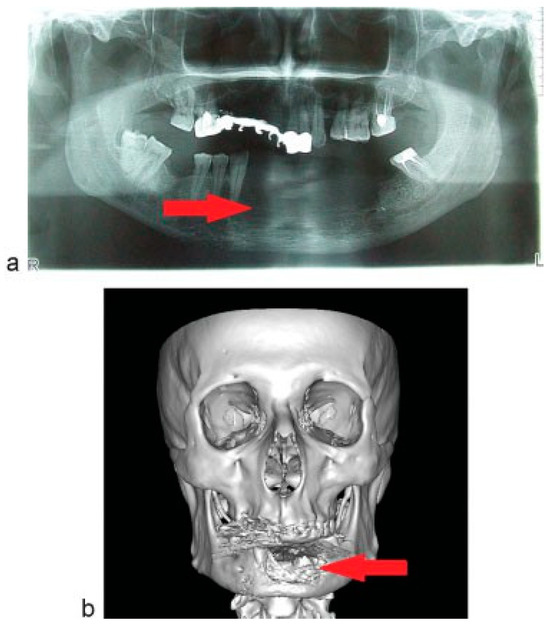

A 56-year-old man presents with complains of lesion in the symphysis of the mandible. Upon anamnesis, first signs of disease noted a year ago after the extraction of the 31st and 32th teeth. The tumor developed within the socket after tooth extraction. The tumor was “excochleated”, and a year later the tumor recurred. Clinically, the tumor was found in the region of alveolar process limited by premolars and spreading to oral mucosa of the floor of the mouth (Figure 1a,b). Orthopantomogram (OPG) and computed tomographic (CT) scan showed the area of bone erosion (Figure 2a,b).

Figure 2. (a) Preoperative radiological picture: OPG. (b) Preoperative radiological picture: 3D CT scan. The area of bone destruction (arrow).